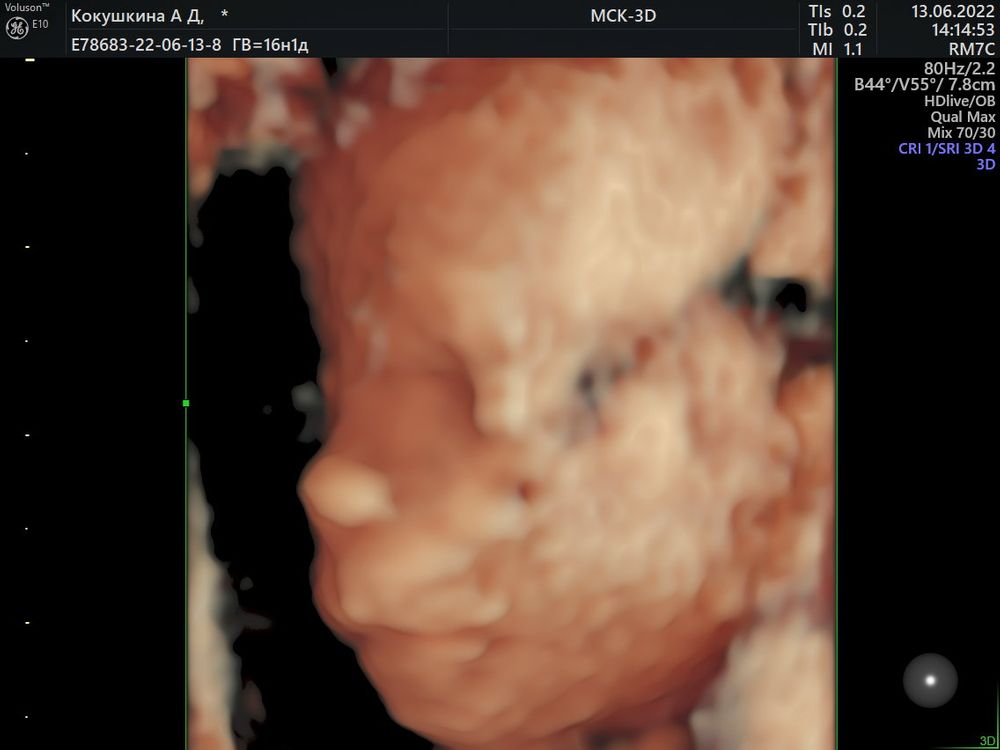

Узнали пол малыша в 16-17 недель🥰

Какая прелесть ! Поздравляю с мальчиком 💐